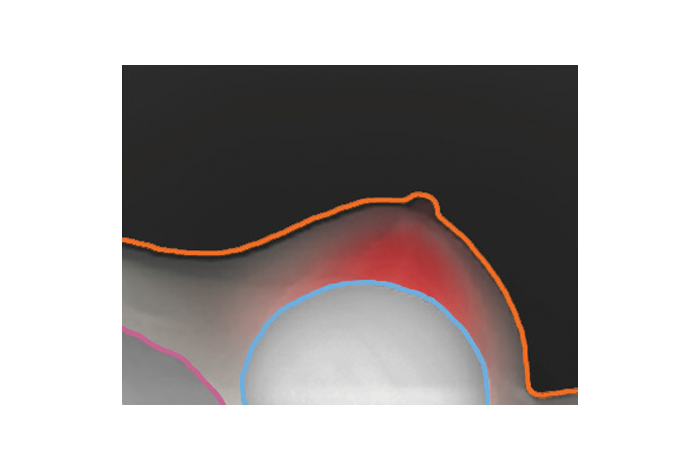

Comfort Comp Compression Reduction

• Reduces patient discomfort during mammograms by leveraging the hysteresis principle.

• Automatically decreases compression force after initial positioning, preserving image quality while enhancing patient comfort.